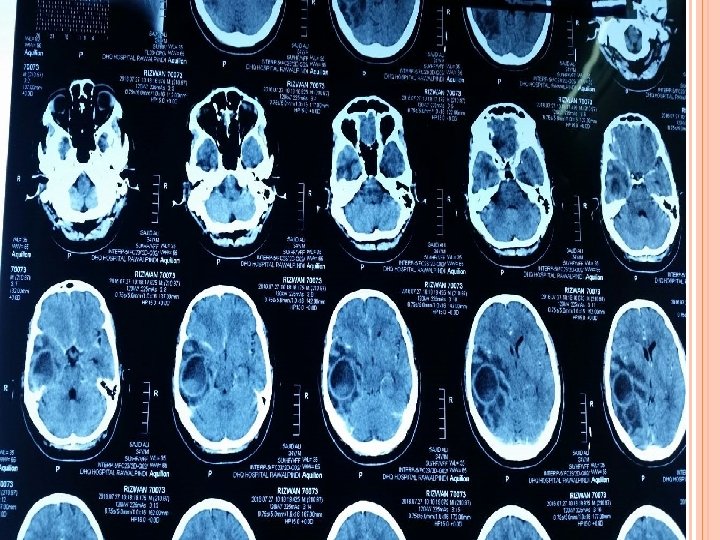

INVESTIGATIONS Blood Tests CBC (TLC-12000/u. L) CRP (3. 2 mg/L) ESR (28 mm/hr). Imaging CT scan Brain ( plain ) CT scan Brain with contrast. MRI Brain with contrast.

CT SCAN BRAIN WITH CONTRAST ( AFTER 1 WEEK)